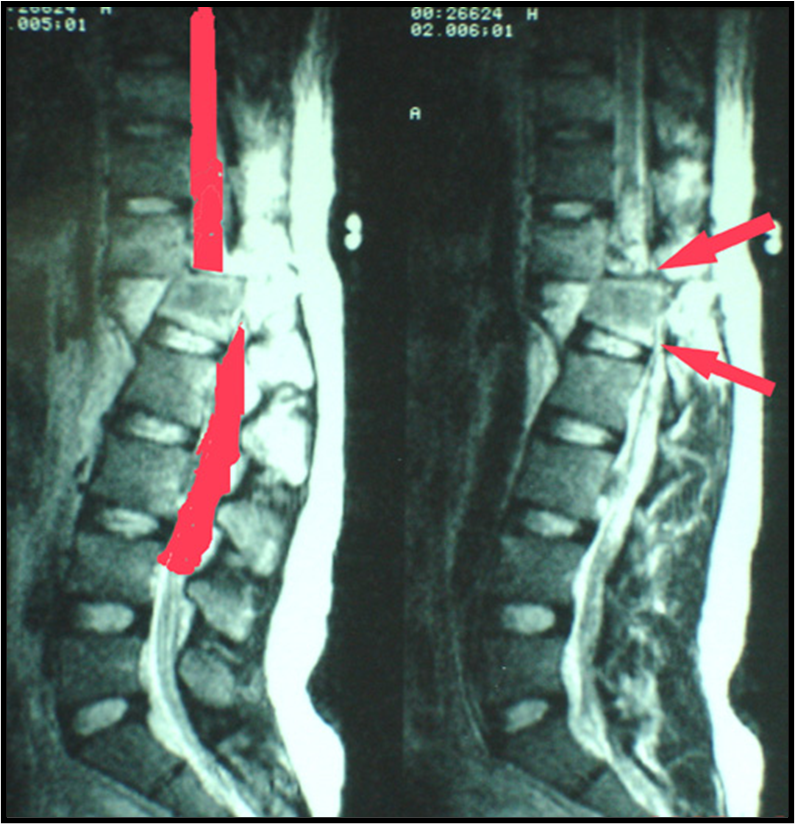

脊柱损伤

脊柱为人体躯干的中轴,保护脊髓神经,躯体活动可引起脊柱的活动。长期卧床易发生压疮,脊柱骨折脱位或手术病人,由于脊柱稳定性差,有继续损伤的危险,不正确的体位改变可导致脊髓损伤、内固定松脱等严重并发症。

护士在翻身时,应采用轴性(滚桶式)翻身,防止脊柱前屈或扭曲;当翻身至对侧时,对侧及背部必须有良好的支撑。